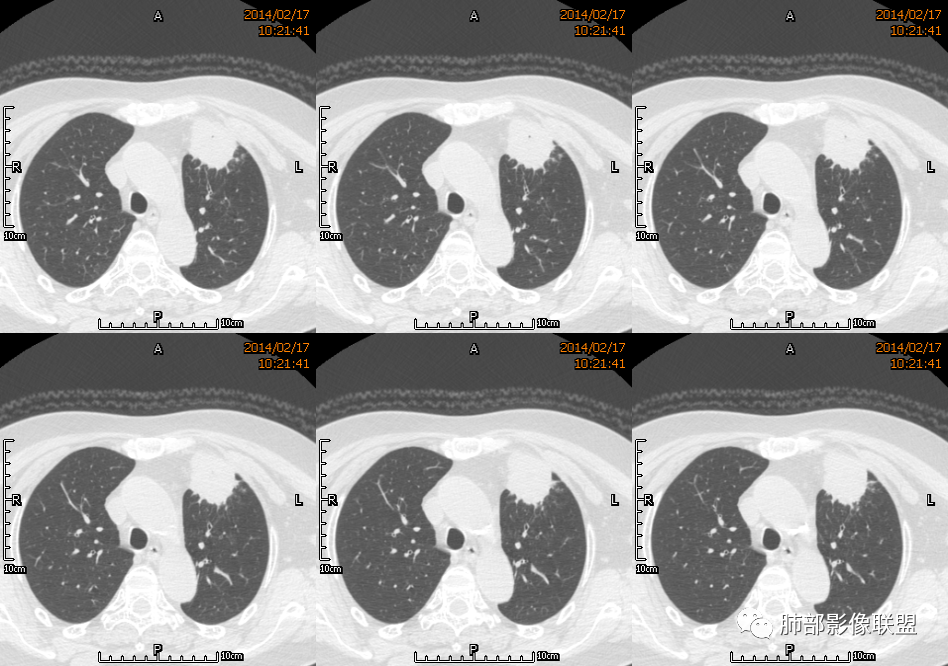

红星: 老年女性,咳嗽咳痰10天,痰中带血4天。左肺上叶前段胸膜下肿块影,沿支气管方向走行以膨胀生长为主,局部有收缩改变,支气管血管绝断,中间有小片状的坏死及小的空洞影,增强扫描病灶明显的强化,病灶周围网格状的小叶间隔增厚。拟左肺上叶前段浸润型腺癌并癌性淋巴管炎。鉴别诊断结核肉芽肿。

水晶石头: 患者老年女性,咳嗽咳痰10天,痰中带血4天余。查血常规白细胞低;肿瘤标志物、凝血功能正常;血生化:蛋白低;C反应蛋白、血沉稍升高。胸部CT:左肺上叶前段胸膜下沿气管支气管走形肿块影,长轴与胸膜平行,见分叶、毛刺、支气管截断、空泡征象。增强明显强化,且见血管造影征及病灶内小灶低密度坏死区。左肺上叶尖后段见一结节灶。综合考虑恶性病变可能大,腺癌或淋巴瘤可能。鉴别诊断肺脓肿。

宇宙星空: 外大内小,近端支气管壁增厚,爬树征,内部坏死不均匀,都比较典型了。支持结核,鉴别炎性肉芽肿、慢性脓肿。

2.左肺上叶前段胸膜下块状影,不规则呈“逗点样”延向肺门区,边界清楚,未见分叶、毛刺及张力,表面不规则棘突,状如“火焰”或“日冕”。相邻胸膜增厚,未见栽赃、卫星病灶。

3.病灶密度不均,中央坏死液化并见气泡影,支气管及血管贴边进入,较均匀环形强化(显示多层结构),未见明确壁结节。

4.肺门纵隔未见肿大淋巴结。